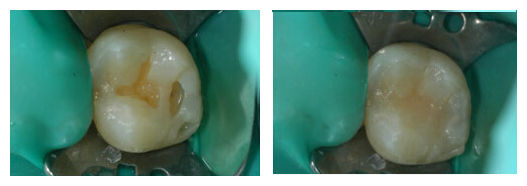

补牙后还会疼吗?

天津海德堡口腔医院专家指出,牙齿是具有生物特性的器官,治疗牙病时必须注意牙齿特别是牙髓处于什么样的状态,从而采取适宜的治疗方法。如果龋病的细菌或其毒性产物已波及到牙髓,引起慢性牙髓炎,不经过合理处理,而盲目填补龋洞,常会产生间断性牙痛,并可能发展为急性牙髓炎,发生剧烈牙痛,也可能逐渐侵袭牙髓产生渐进的牙髓坏死,牙痛反而减轻或消失,但时隔不久往往再次发生急性炎症——急性很尖周炎。

补牙,又称充填术。目前常用的充填材料(补牙材料)虽对人体无害,但对牙髓有一定的刺激作用,如龋洞太深时用护髓材料护髓,就会因分离出某些物质刺激牙髓而发生疼痛;复合树脂,对牙髓也有刺激作用,这些材料不能直接充填较深的龋洞,必须先用无刺激的材料垫上一层后再选用其他材料充填,否则就会导致充填后疼痛。

因此对于牙髓有炎症的龋洞充填必须慎重,对慢性或急性牙髓炎经很管治疗或牙髓治疗后出现的疼痛,可能是由于操作粗暴或药物刺激而引起,也可能由于治疗不慎遗留下的感染继续发生而造成,所以同样患龋齿的人有人可以一次充填完,而有的人要复诊几次换药,待牙病完全无痛许后才能充填。对那些因患牙髓炎或根尖周炎而补的牙常常龋洞较大,而且因失去了牙髓的营养,牙齿会因脱水而变脆,易发生冠折,所以一定要注意。

牙齿烂了洞后,要尽早去医院补牙。牙齿修补好后使用时间的长短,有多种因素。首先是补牙的时机。病人就诊时牙齿龋坏的程度、部位及牙洞的形状都有很大的关系;其次是补牙的材料。不同的材料与牙洞的粘结性有所不同;最后是补牙前牙洞的处理。具体补牙后能用多久也是因人而异的,保护得当自然使用时间长。